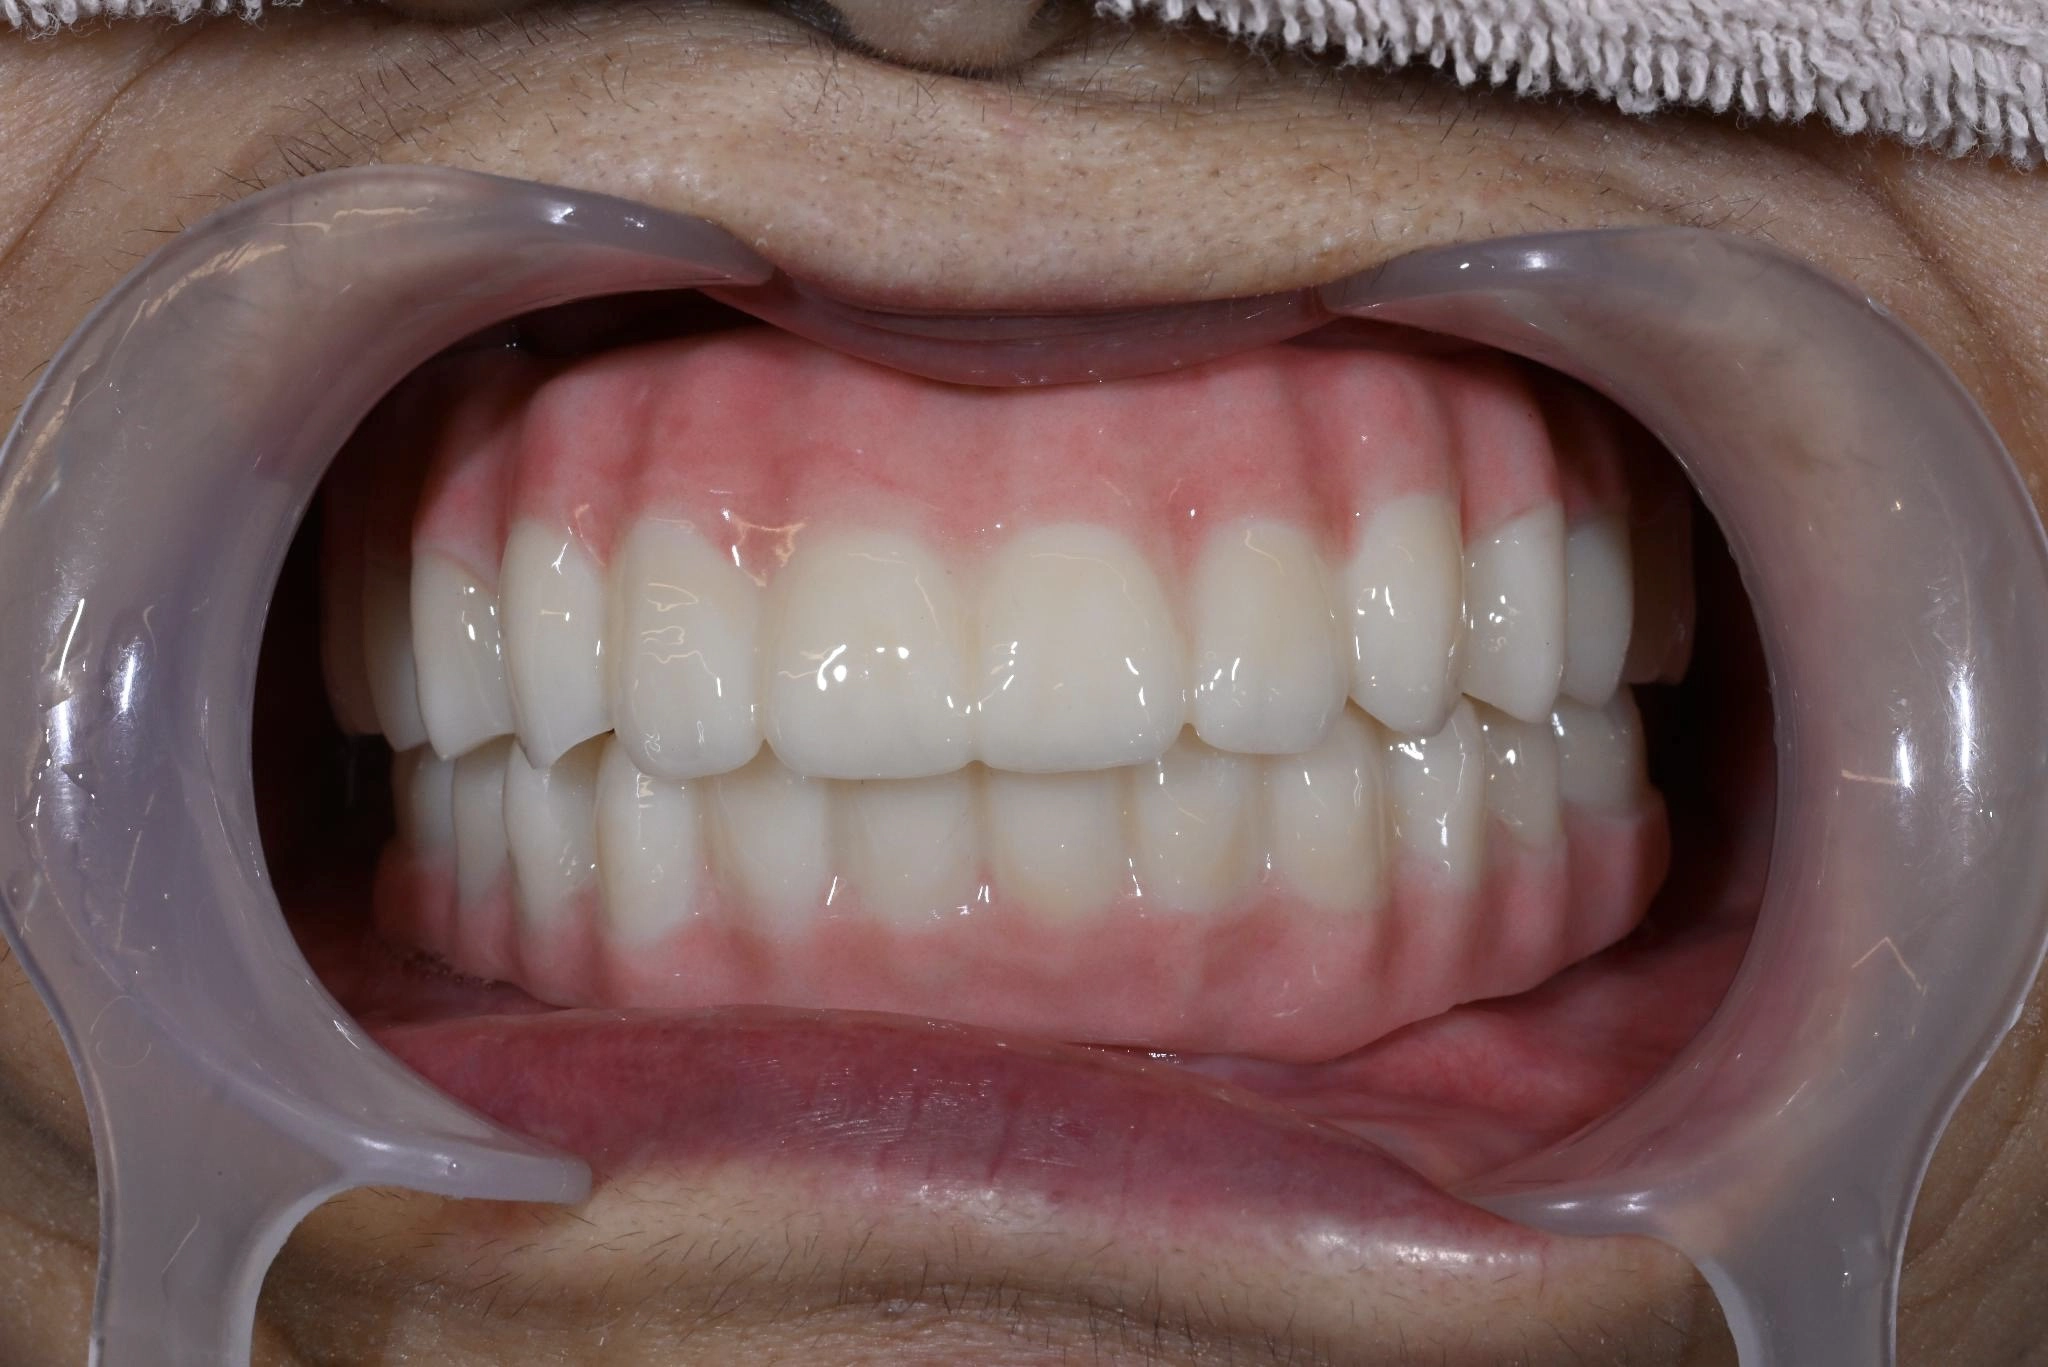

術後

内容 :上下顎オールオン4ザイゴマ4

費用 :5,500,000円

※モニター価格

期間 :半年

リスク:出血・腫れ・痺れ・痛み

長年歯について悩んでいました。歯がぐらつくことがあり、治療を行っていました。他院で入れ歯を作りましたが、噛み合わせが合わず、食事の際に噛みにくさを感じていました。

持病があるため、手術を受けられる状態か相談しに行くことにしました。

話を聞いてみるとスッタッフの方が親切で、不安な部分を確認しながら相談できました。

術中は特に痛みを感じることはなく、気づいたらいつの間にか終わっていました。術後、これまでの歯の状態と比べて綺麗になっていてとても満足しています。